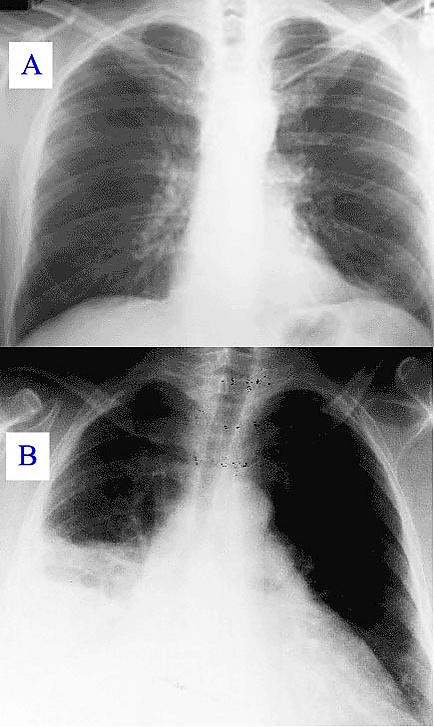

Основными методами диагностики являются рентгенологическое исследование лёгких и исследование мокроты, основным методом лечения — антибактериальная терапия. Поздняя диагностика и задержка с началом антибактериальной терапии ухудшают прогноз заболевания. В некоторых случаях возможен смертельный исход.

«Типичная» пневмония характеризуется резким подъёмом температуры, кашлем с обильным выделением гнойной мокроты и, в некоторых случаях, плевральной боли. При исследовании: укорочение перкуторного звука, жёсткое дыхание, усиленная бронхофония, усиленное голосовое дрожание, сначала сухие, а затем влажные, крепитирующие хрипы, затемнение на рентгенограмме. Такую пневмонию вызывают Streptococcus pneumoniae, Haemophilus influenzae, Escherichia coli, Klebsiella pneumoniae[22].

- Рентгенография грудной клетки[23]